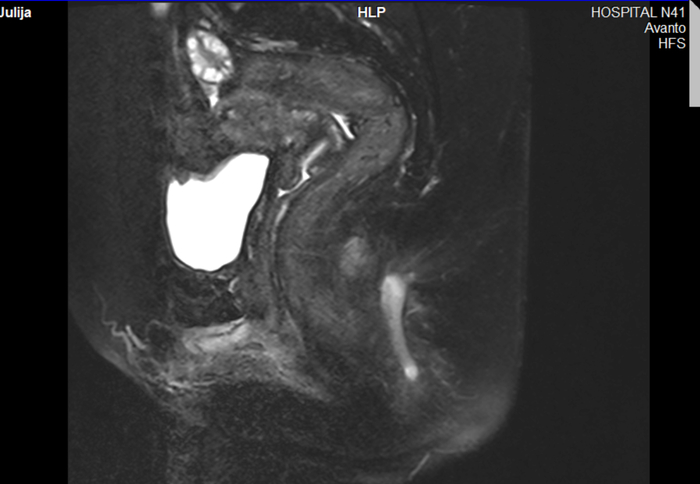

Сейчас у неё всё хорошо. Рана зажила вполне приемлемо, свища не видно, держание улучшилось. Конечно, не могу гарантировать, что потом что-то не всплывет, но по МРТ там сплошной рубец, без свищей. Хотя в глубине души я понимаю - он спрятался глубоко внутри.